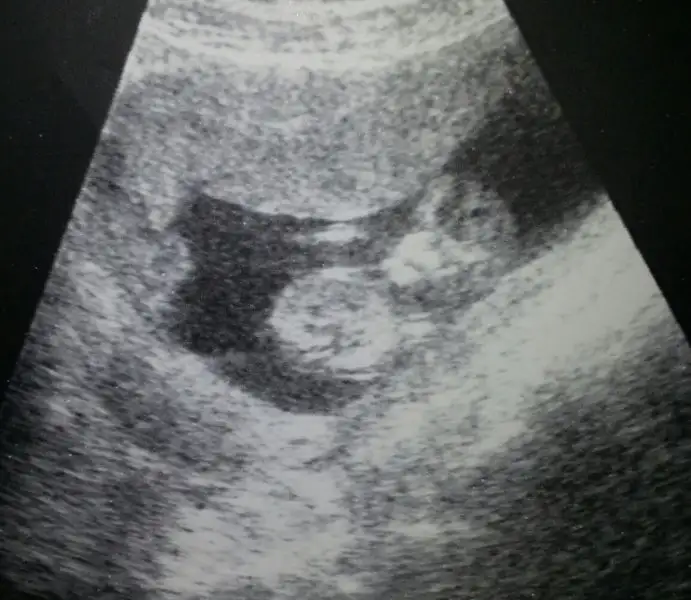

Erkek bence.Herkese sağlıklı ve huzurlu günler diliyorum hanımlar. Bir de bana cinsiyet tahmini yapar mısınız rica etsem acaba :)Eki Görüntüle 2146302

Bana da erkek gibi geldi.teyzoşları bunlarda bugün çekildiğimiz fotoğraflarımız

Erkek gibi geldi bana :)

inşallah kızlar bakalım kız mı olacak erkekmi. doktor diyo ki kız olsun babasına aşık olur, şimdi eşinin istediği olursa 2.yi yapmaz diyo eşimeBana da erkek gibi geldi.